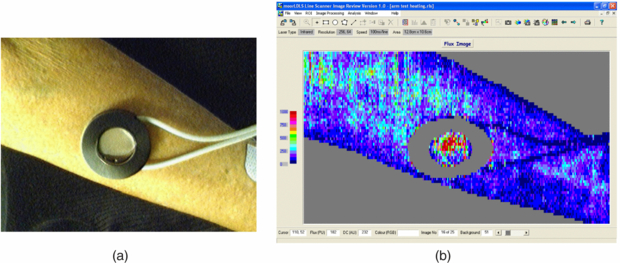

There are a range of protocols for testing endothelial function using LDPI and these include local skin heating (water heater placed on the skin site, usually the forearm, and with an optical aperture for blood flow imaging, figure 5), iontophoresis (vasoactive compounds pass through the skin on a low level dc current stimulation, usually acetylcholine for endothelial-dependent vasodilatation (Ach) and sodium nitroprusside (SNP) for endothelial-independent vasodilatation as a reference comparator) (Morris et al 1995, Anderson et al 2004, Turner et al 2008), and post-occlusion reactive hyperaemia (flush characteristics assessed after usually a 5 min arm pressure cuff occlusion of at least 250 mmHg). Each of these methods provides different information relating to the health of the endothelium. Choice of measurement site and measurement reproducibility are very important considerations (Kubli et al 2000), with a coefficient of variation typically of 17% found for acetylcholine iontophoresis with LDPI (Newton et al 2001b). Normative data are important to establish for each measurement facility, protocol, local study population and age range (Elherik et al 2003, Millet et al 2012).

Figure 5. (a) Forearm skin measurement site with skin heater filled with heated water at set study temperature to achieve local vasodilatation (temperature set typically to 41 °C). The water chamber has a plastic cover which allows the laser system to measure the corresponding perfusion changes i.e. reactive hyperthermia (b). Over a heating period of typically 30 min an initial spike in perfusion is expected near the start of heating (attributed to the axon reflex) and then reaching a peak level. This heating type challenge test can also be measured using LDF spot perfusion techniques at the forearm microvasculature, and comparing peak perfusion during heating to baseline perfusion can give information on microvascular endothelial dysfunction, for example in patients with wider coronary heart disease (Agarwal et al 2010, 2012).